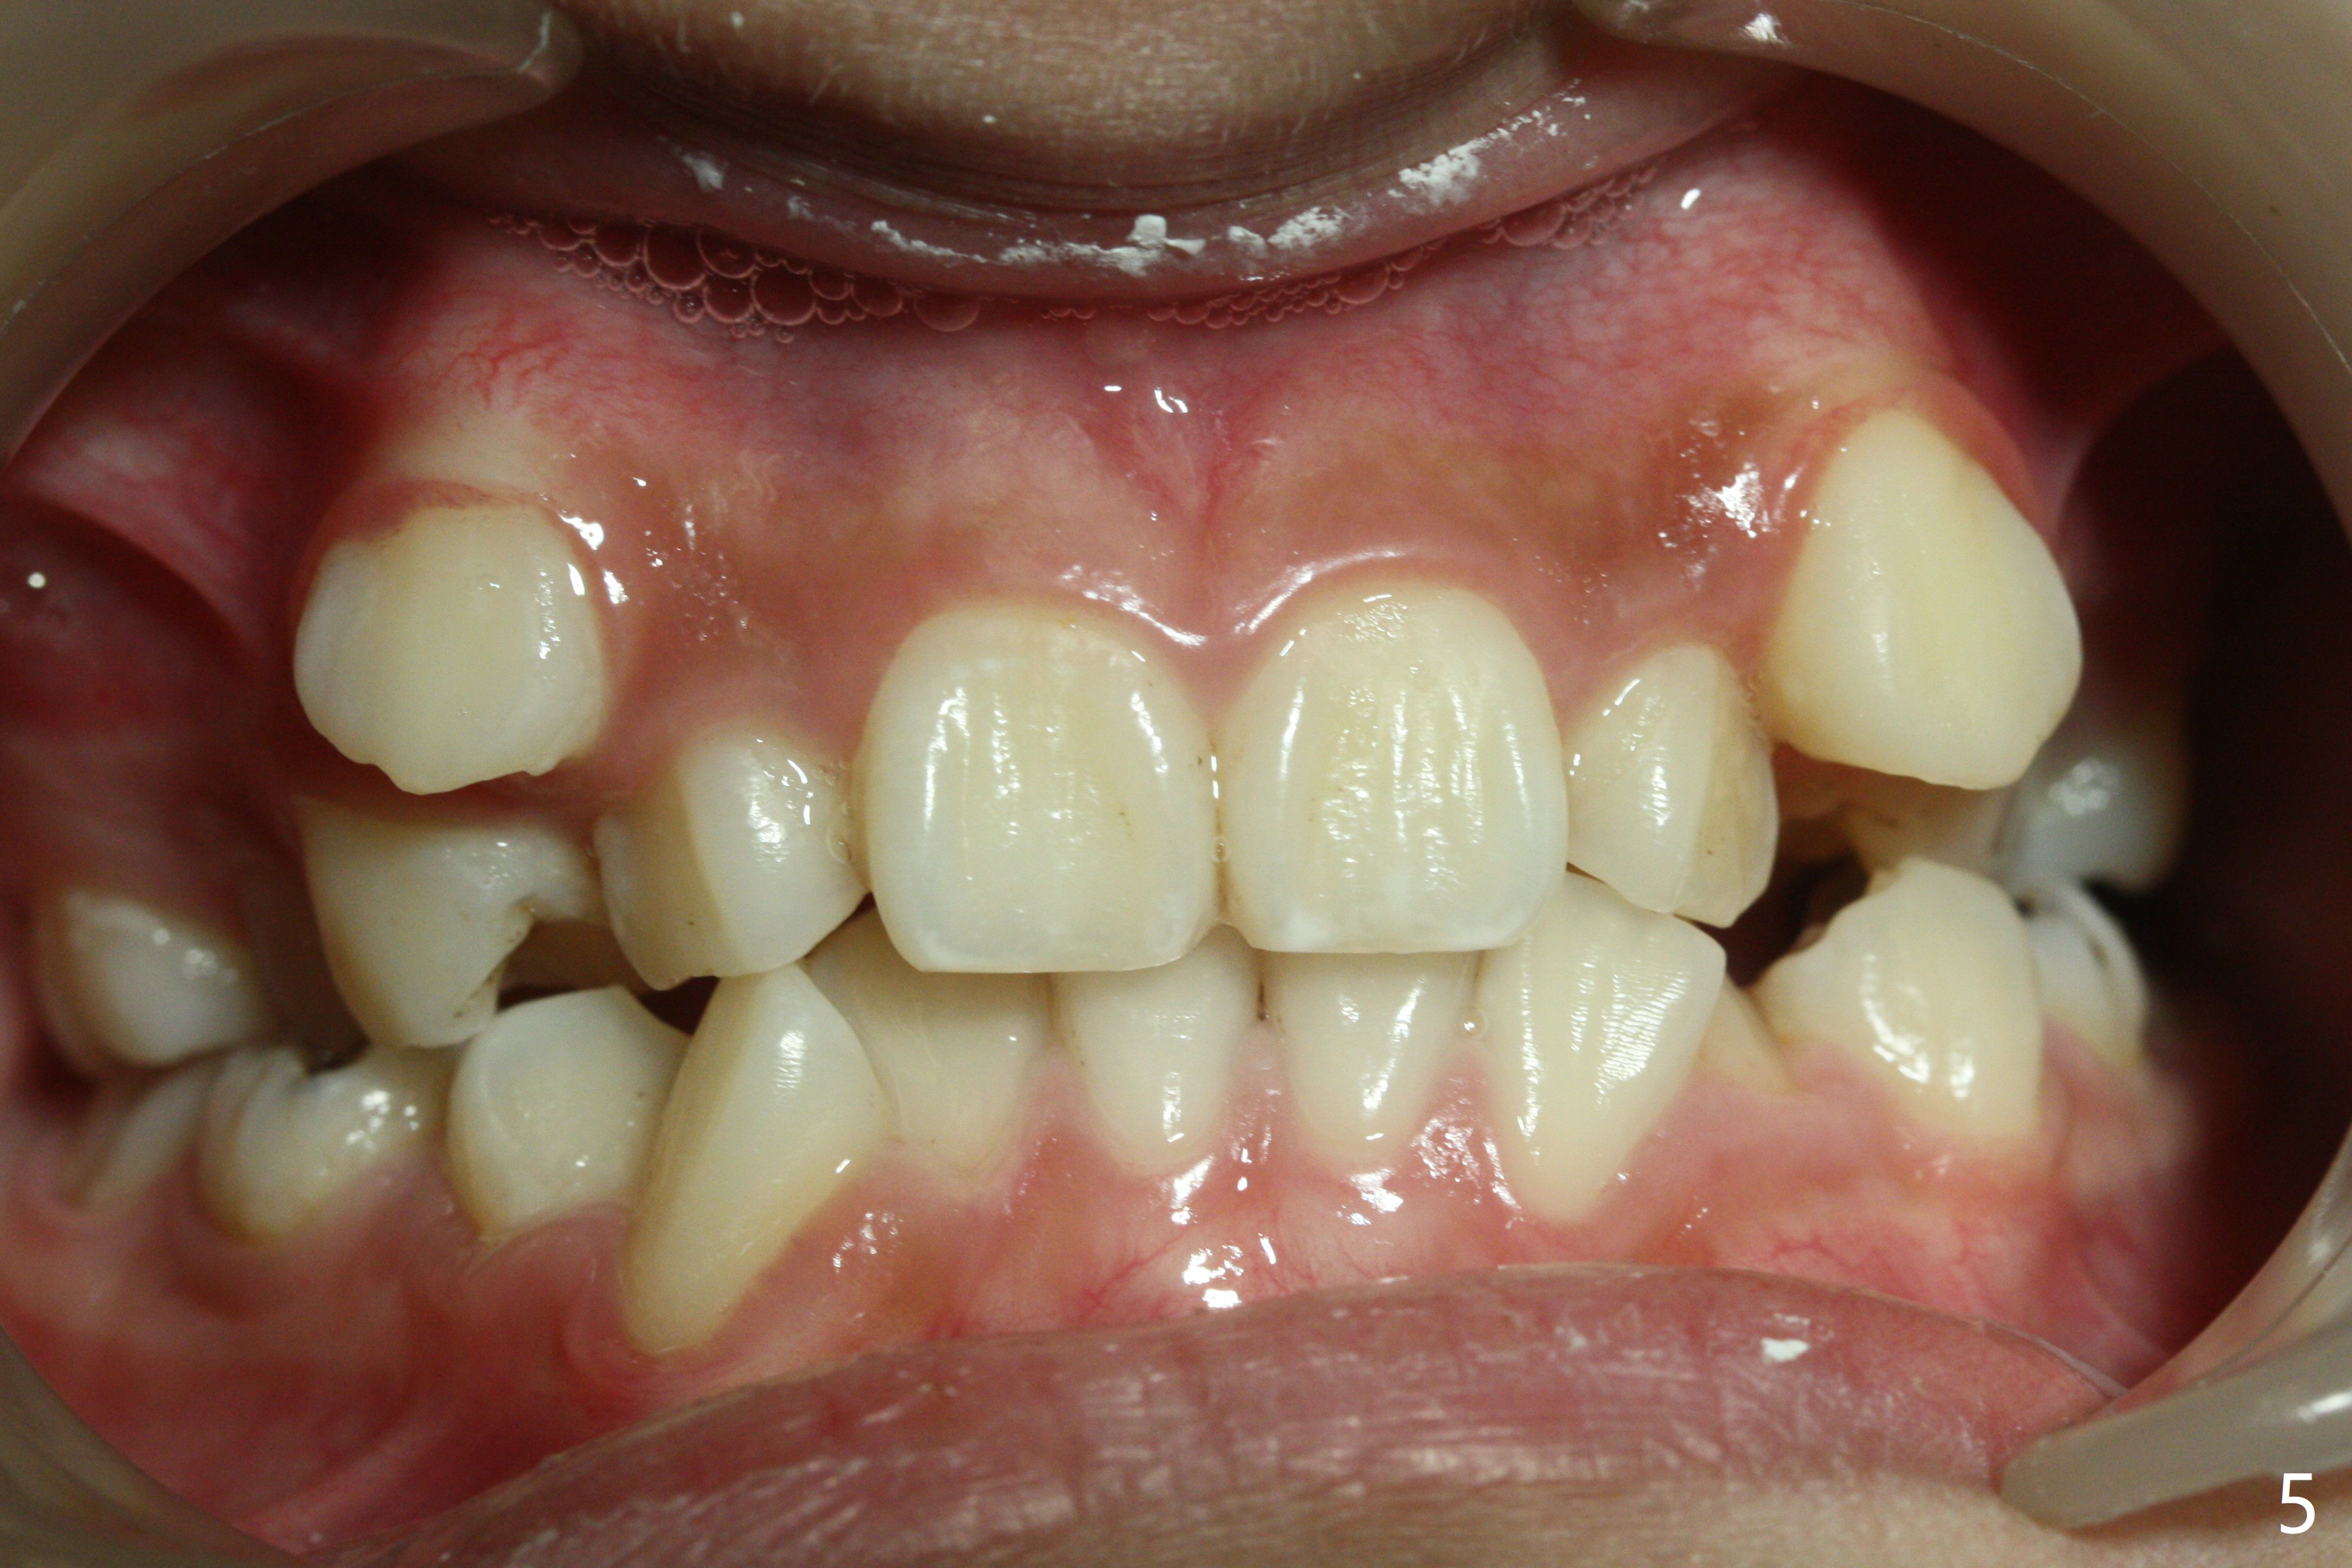

Severe crowding with normal facial profile appears to dictate extraction of 4 bicuspids and of the lower 2nd primary molars (Fig.1-11).  Since there is no time for banding before school, delay in orthodontic treatment post extraction will lose space?

Dear Dr. Shaughnessy: can you open the following link?  I would like to try to extract 4 bicuspids and 2 lower primary 2nd molars and let the canines shift by themselves.  But I wonder whether the 2nd permanent bicuspids, especially the upper ones, may shift mesially instead.  How would you like to handle the situation?

In fact, the family is moving out of state.  To accomplish automatic shifting before seeing a new dentist, extraction is executed.  At the mother's request, six teeth are removed.